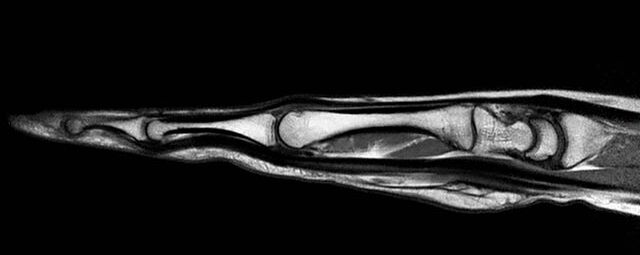

- Beurteilung von Knochen, Bändern und anderen Weichteilstrukturen der Gelenke nach Unfall.

- Arthrosediagnostik (Knorpelschaden)

- Abklärung Bandscheibenvorfall

- Beurteilung Einengung des Rückenmarkkanals oder der Neuroforamina im Rahmen der degenerativen Wirbelsäulenerkrankung

- Tumor-/Entzündungsdiagnostik